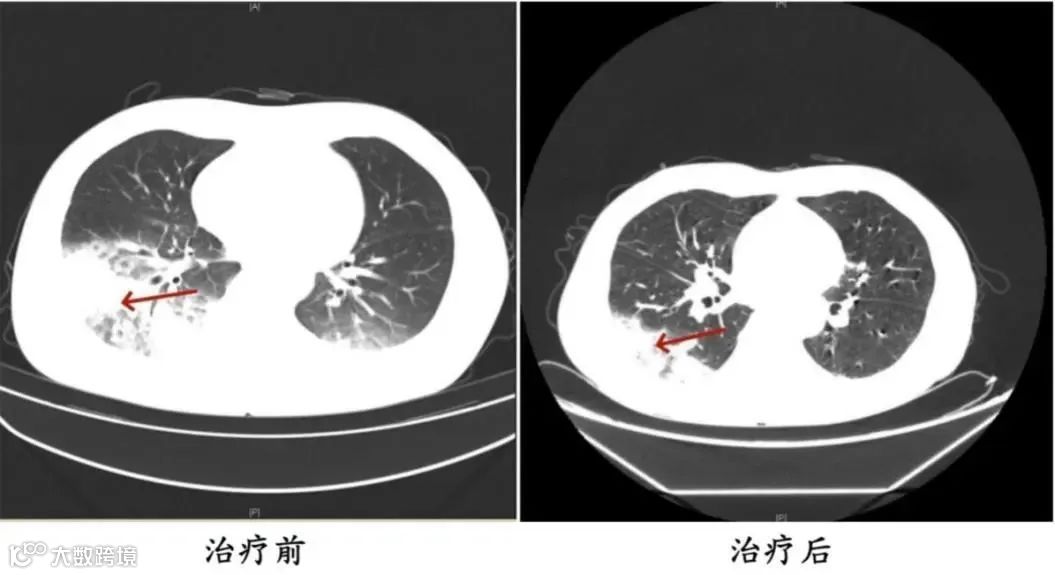

家人见状,立即将他送医。胸部CT显示李先生的左肺已出现大面积白色影像,几乎占据一半肺部。经过检测,最终确认是嗜肺军团菌肺炎。

李先生肺部治疗前与治疗后的对比